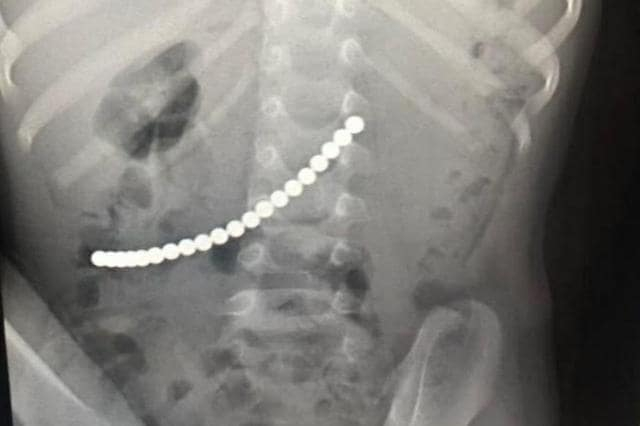

Когда ребенок пожаловался на боли в животе, медики заподозрили у мальчика кишечную инфекцию, ему дали обезболивающее. Но лекарство не помогло, симптомы не прошли, и ребенка положили в стационарное отделение больницы. Маленькому пациенту назначили лечение и процедуры, он принимал капельницы, ему ставили клизмы, пытаясь очистить организм. При этом никому не приходило в голову назначить рентген. Его сделали спустя неделю, а результате в теле юного пациента были обнаружены магниты. К тому времени дошкольник едва не умер от перитонита.

К счастью, все посторонние предметы были удалены, и сейчас здоровью 4-летнего мальчика ничего не угрожает.